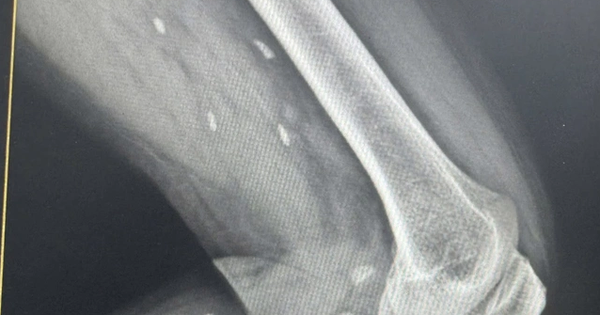

Kết quả thăm khám cho thấy ông Lưu bị viêm túi mật. Khi làm thêm các xét nghiệm chuyên sâu, bác sĩ phát hiện ông còn có sỏi ống mật chủ và chỉ định phẫu thuật. Ca mổ diễn ra thuận lợi, những ngày đầu hồi phục đúng tiến triển dự kiến. Thế nhưng, trong một lần kiểm tra định kỳ lượng dịch mật dẫn lưu qua ống T, bác sĩ trực bất ngờ phát hiện trong dòng mật trong suốt có một sinh vật nhỏ đang ngọ nguậy.

Dựa vào kinh nghiệm lâm sàng, bác sĩ nhanh chóng xác định đó là sán lá gan, còn gọi là sán lá gan nhỏ hay Clonorchis sinensis. Khi được hỏi kỹ về tiền sử ăn uống, ông Lưu mới nhớ ra rằng khoảng nửa năm trước, trong một buổi tụ tập bạn bè, ông từng ăn cá nước ngọt sống. Vì tin rằng cá tươi và đã được xử lý sạch nên ông không chút do dự, không ngờ lại vô tình “rước” ký sinh trùng vào người.

Các bác sĩ kết luận, tình trạng viêm túi mật và sỏi đường mật của bệnh nhân có liên quan mật thiết đến nhiễm sán lá gan từ món cá sống này. Theo bác sĩ, sán lá gan ký sinh và sinh sản trong đường mật, các chất chuyển hóa của chúng cùng sự kích thích cơ học liên tục sẽ làm tổn thương niêm mạc ống mật, gây viêm, ứ mật và lâu dần thúc đẩy quá trình hình thành sỏi.